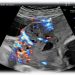

Webinar SIEOG di Dicembre 2023: screening delle cardiopatie congenite nel primo trimestre

Per il mese di Dicembre SIEOG Giovani presenta il Webinar sullo screening delle cardiopatie congenit